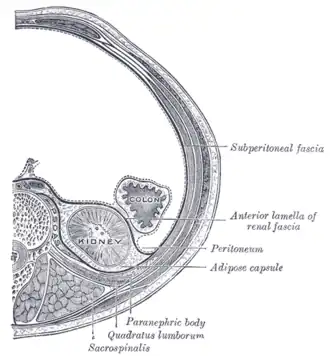

Diagram of a transverse section of the posterior abdominal wall, to show the disposition of the lumbodorsal fascia

Diagram of a transverse section of the posterior abdominal wall, to show the disposition of the lumbodorsal fascia -

Transverse section, showing the relations of the capsule of the kidney

Transverse section, showing the relations of the capsule of the kidney -